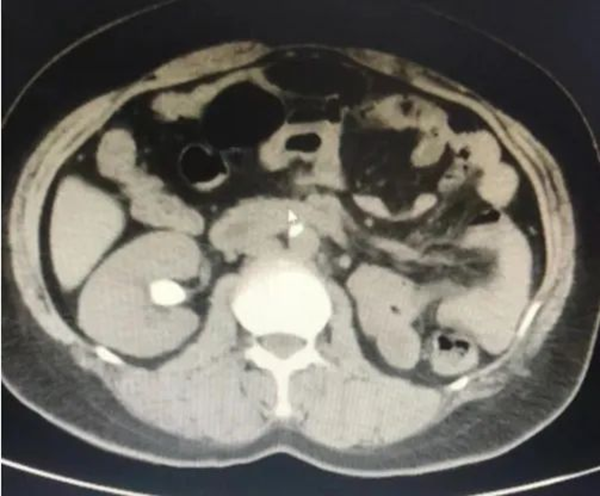

萬般絕望之際,王女士多方打聽,在朋友的推薦下來到徐州市中醫(yī)院泌尿外科就診。入院后,經(jīng)CT檢查顯示,王女士右腎下盞結(jié)石,直徑為2.1*1.6cm,結(jié)石CT值1360Hu,初步判斷為草酸鈣結(jié)石。

右腎結(jié)石(術(shù)前)